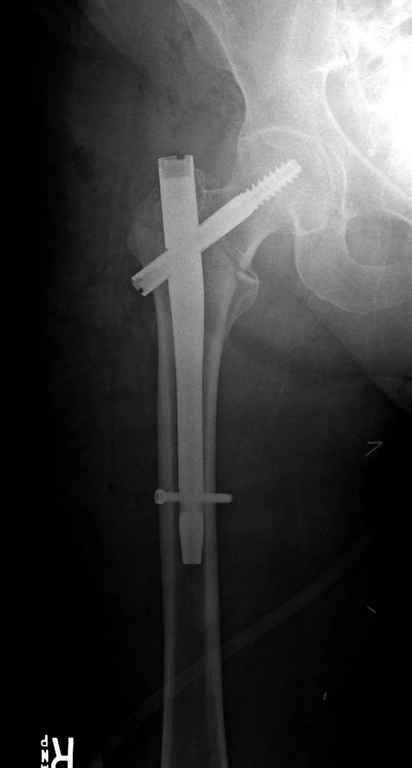

В приложении похожий пример, к счастью, пациентка появилась не после, а "за полчаса" до протрузии. Пересинтезировали с исправлением ошибок.

Вашему вниманию представляется похожий случай, пациентке 70, осложнился в течение одного месяца после операции. Ревизия с заменой сустава, кабельная фиксация на трохантер. При установке в дистальном диафизе обнаружен тонкий кортикальный слой и сделана профилактика от возможного перелома аллографтом.